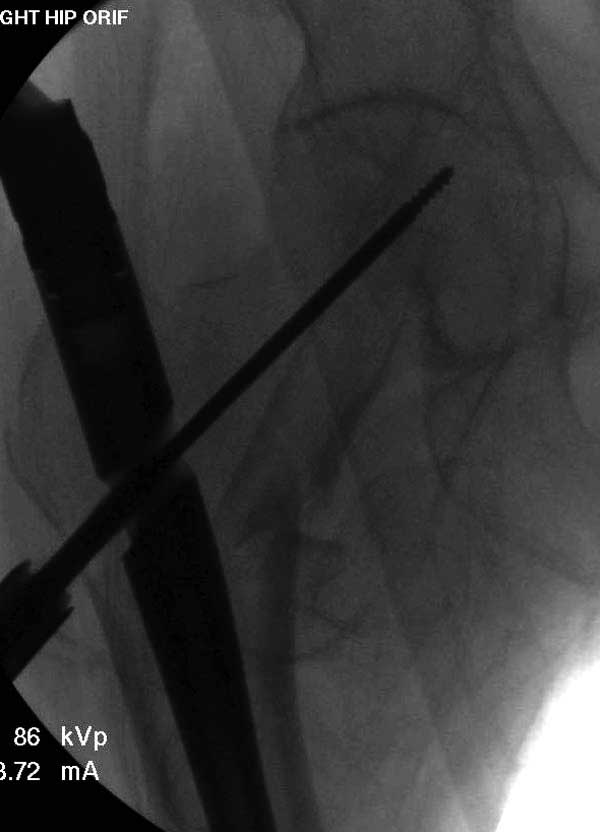

Первые снимки показывают технические погрешности установки DHS. Не была достигнута репозиция, конечность в флексии и шейка в ротации. Сегодня все меньше обращают внимание на параметры для оценки репозиции (S контуры Lowell в обеих проекциях и Garden Alignment Index, в норме 155 и 180 градусов), хотя такие простые тесты помогли бы дорепонировать смещение. Винт находится сзади в головке, что при нагрузке поменяет вектор и вместо компрессии в линии перелома срежет головку-Cut Out!